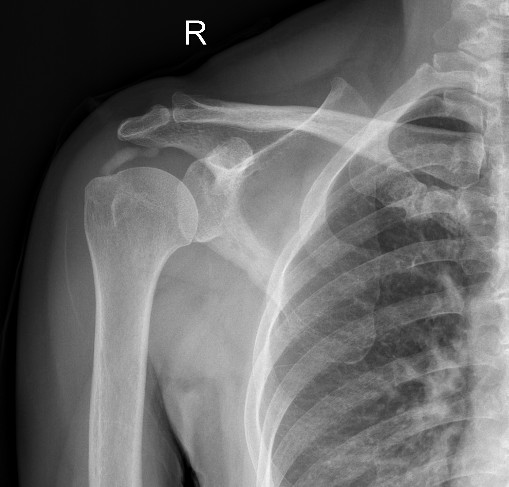

陆阿姨于今年7月来到广西中医药大学附属瑞康医院关节与运动医学科门诊就医,经过医生的详细检查,拍X光片后发现右肩部肩袖区有明显的钙化灶,才知道自己得的是“右肩关节钙化性肌腱炎”,陆阿姨在震惊之余也看到了希望,关节与运动医学科李书振主任认真细致地跟她分析了病情及解决方案,由于长时间的求医路和肩部疼痛难忍影响到了正常生活,陆阿姨马上住进了瑞康医院关节与运动医学科,并接受了“经肩关节镜微创手术”治疗,手术中从陆阿姨的肩膀里竟然挤出了许多白色的牙膏样物质,这就是已经钙化的肌腱组织。手术当晚陆阿姨的右肩疼痛明显减轻,3年来终于可以睡个好觉了,现在陆阿姨的肩部病痛已经彻底解决,已经恢复了正常生活。

术前X光片显示肩袖区钙化灶